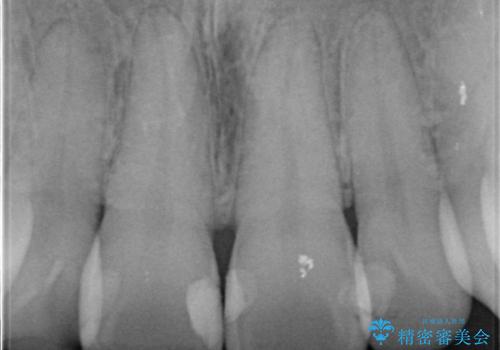

前歯の劣化したコンポジットレジン修復をセラミッククラウンへ

- 数年前に前歯の虫歯治療し、コンポジットレジン修復がなされてい箇所の審美障害の改善を希望され来院されました。

再度レジン修復を行うか、劣化のスピードは遅いが歯の削合が必要なセラミッククラウンの治療の選択肢をご提案し、今後のやりかえの心配の少ないセラミッククラウン治療を希望されました。